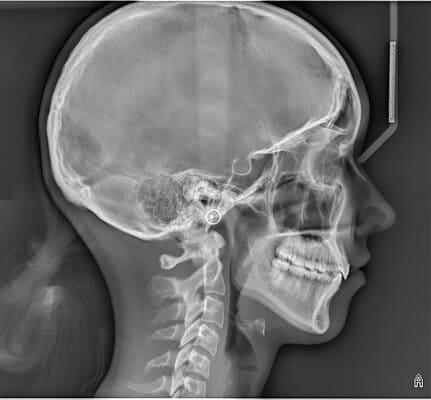

Дівчинка 7 років, перше вересня, гойдалка… Вивих постійного зуба: якщо в такій ситуації зволікати, дитина може втрати постійний зуб назавжди. Батькам порекомендували нас і пацієнти одразу приїхали. Через складність і травматичність процедур вирішено проводити лікування в анестезіологічному супроводі. Зуб поставлений на місце (репонований), проведена хірургічна обробка і ушивання рани губи. Останнє фото через рік після травми: зуб на місці і корінь продовжує розвиватись, губа повністю загоїлась